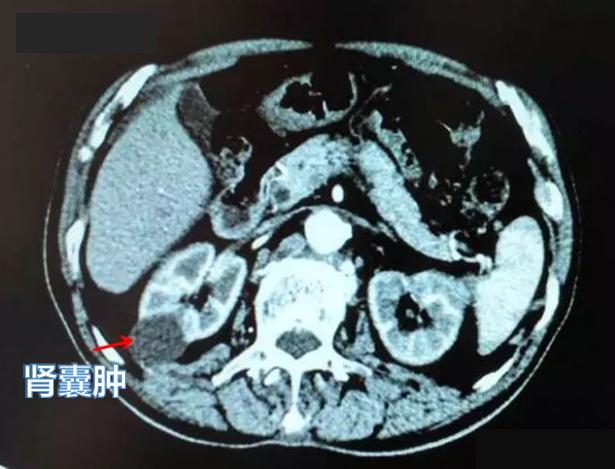

右侧肾囊肿

肾囊肿,医学上又称为囊肿性肾脏病,是一种常见的、由于肾脏发生先天性或后天性结构异常而导致的囊性病变。据研究显示,人类肾囊肿患病率存在地区、民族等差异,在中国北京地区超过17000例的体检人群中,肾囊肿发病率为4.16%;在海湾地区8个国家超过8500例体检者中,发病率为4.2%;而日本的研究者则发现,日本的发病率为11.9%。通俗地讲,肾囊肿就是肾脏内出现大小数量不等、与外界不相通的"水泡",虽然也是"肿",但一般认为肾囊肿并非肾肿瘤,也极少会发展为恶性病变。